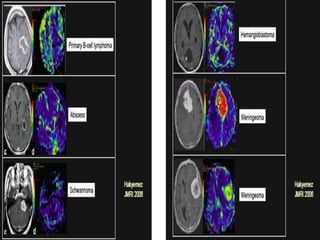

PMR TIC (lower right) and rCBV

map (left) demonstrate very

high microvascular blood

volume. The low return to

baseline of the lesion TIC (green

curve) compared with normal

brain (purple curve) is

characteristic of high first-pass

leak in an extra-axial lesion

without a BBB. In this case, the

high permeability also produces

prominent enhancement on the

delayed post-Gd T1-weighted

image (upper right) in a pattern

strongly suggestive of

meningioma, but the distinctive

PMR findings illustrated can be

very helpful in the differential

diagnosis of less classical

appearing lesions.

Comparison of rCBV color map

(upper right) and TIC (lower

right) in regions of interest

selected within the dural-based

enhancing lesion (lower left,

purple) and an appropriate

region of interest in the

contralateral white matter

(lower left, green) demonstrate

the characteristic high first-pass

leak of a nonglial tumor (TIC)

and blood volume only

minimally higher than white

matter (TIC and rCBV color map).

In combination with the

appearance on coronal post-Gd

T1-weighted image (upper left),

the perfusion imaging strongly

suggests dural metastasis,

confirmed at biopsy to be from

non–small cell lung carcinoma.